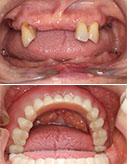

“牙缝大”不开心-瓷贴面7天让你美丽无忧

15岁小帅哥全口虫牙 根管修复露笑颜

不要等牙疼时才想起保护

龋齿不可大意 牙髓炎太可怕

治疗牙周病 还得早着手

只想变美 那就现在

健康爱美的大门前没有“男士止步”

收拾小龅牙 最正确的决定

小小种植牙 托起大梦想

种牙种健康 最美夕阳红